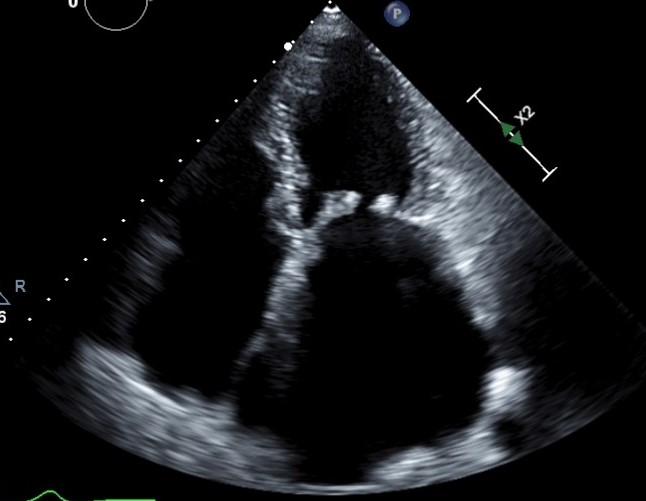

Image- A patient with rheumatic heart disease. Echocardiography helped in diagnosis of valve problems.